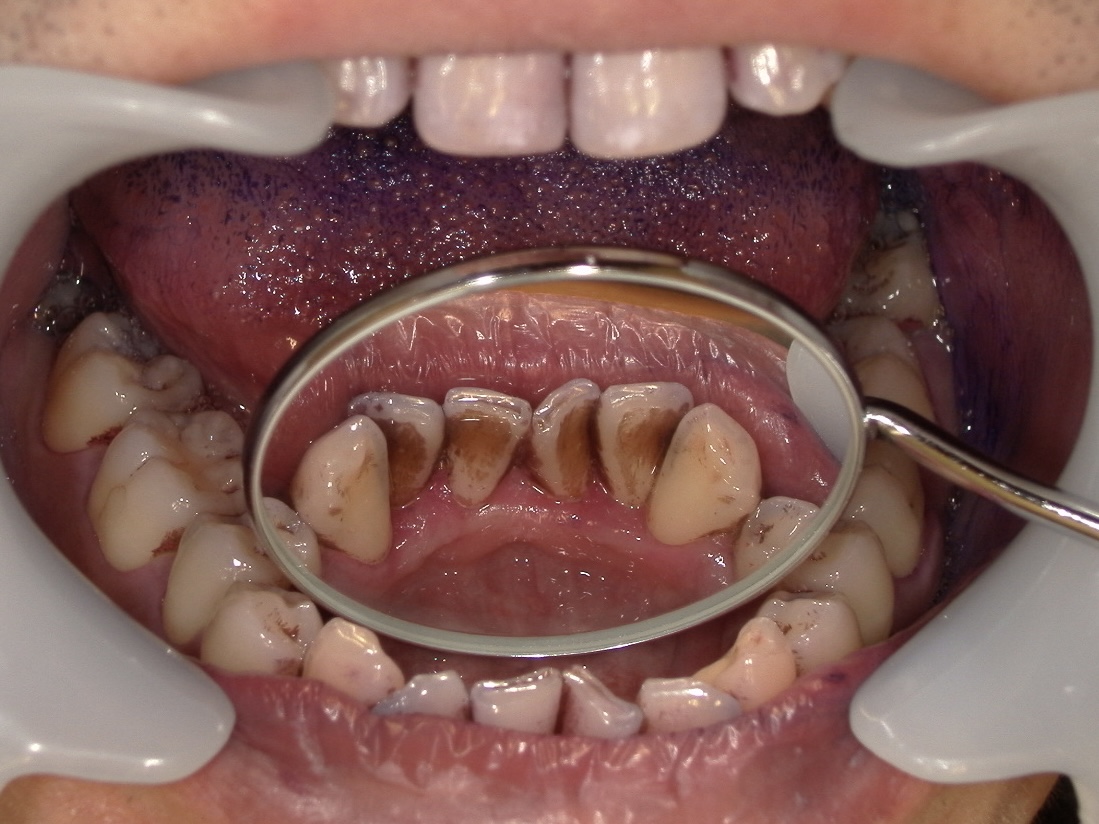

◆クリーニング前の状態(染め出し後)

当院ではクリーニングを行う前に、染め出しを行います。歯垢を染めることによって、「こんな場所にこんなにみがき残しがありますよ」と可視化することで患者様により分かりやすく見ていただくことができます。

写真をご覧いただくと分かる通り、

下の前歯の裏側には染め出し液が広範囲に付着しているのが分かります。

この部分は、

鏡ではほとんど見えない

舌が常に当たる

唾液腺が近く、歯石が付きやすい

という特徴があり、セルフケアだけで完全にきれいに保つのが非常に難しい部位です。